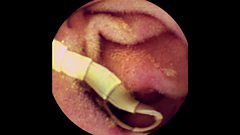

Tapeworm in Michael's gut

Duration: 01:37